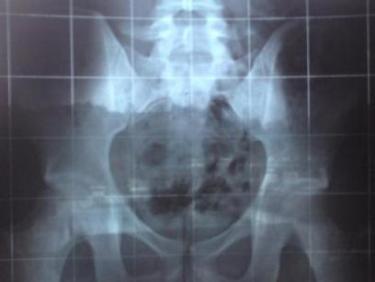

das hüftröngten ist ganz "frisch":

was sagt ihr zum beckenschiefstand bzw. beckenverwringung?

ich finds komisch, dass das steißbein (etwas schwer zu sehen) nicht genau hinter der symphyse (wo hüfte links und rechts vorne zusammenkommen) liegt, sonder links.

hüftröngten wurde gemacht auch wegen meinen andauernden schmerzen beim rechten gesäßmuskel (vorwiegend glaub ich gluteus medius, bin mir aber net ganz sicher, könnte auch piriformis sein ??) und rechtem lws bereich.

isg blockaden hab ich auch immer öfter.

sakroilitis wurde bei mrt (aber leider ohne kontrastmittel, naja) ausgeschlossen.

der beckenschiefstand bzw. verwringung macht mir deswegen sorgen, weil ich eben schon einen prolaps über dem kreuzbein l5/s1 habe.

glaubt ihr, es könnte eventuell auch eine beinverkürzung vorliegen?